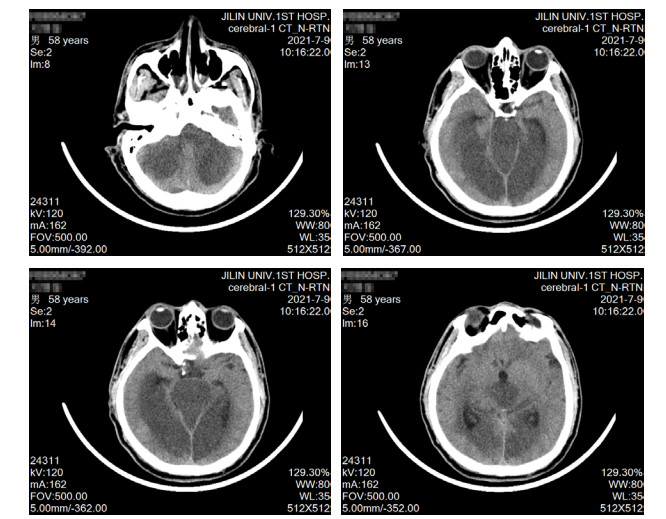

1 资料与方法患者男性,58岁,因“头晕、黑矇3 d,意识不清15 h”于2021-07-07 18:53急诊以“意识障碍待查”收入本院重症医学科。患者3 d前无明显诱因出现头晕、黑矇,共发作7~8次,每次持续5~10 min后自行缓解,上述症状与体位无关,不伴有头痛、耳鸣、视物双影及视物旋转,无发热,曾于当地医院就诊考虑“眩晕症”,给予静点川芎嗪及血栓通后上述症状有所缓解。于入本院前15 h如厕时被家属发现倒地,呼之不应,无抽搐发作,无尿便失禁,无舌咬伤及呕吐,急由120救护车送至当地医院,测体温42.0℃(距离发病1 h),行头部及肺部CT未见明显异常,肝肾功能及降钙素原结果均正常,为求明确诊疗转诊至本院,急诊以“意识障碍待查”收入重症医学科。病程中无咳嗽、咳痰,无尿急、尿频、尿痛,无恶心、呕吐,无腹痛、腹泻。既往史情况:发现高血压病史1年,血压最高160/80 mmHg(1 mmHg=0.133 kPa),未系统诊治及监测。脑梗死病史1年。吸烟史20年,约10支/d,未戒。饮酒史20年,约100 g/d,戒酒1年余。入科查体:体温39.1℃,脉搏114次/min,呼吸23次/min,血压129/80 mmHg,外周血氧饱和度98%(鼻导管吸氧,氧流量3 L/min)。意识不清,GCS评分5分,双侧瞳孔等大同圆,直径约4.5 mm,直接、间接对光反射迟钝,皮肤、巩膜无黄染,咽部无红肿,扁桃体无肿大,气管居中,听诊双肺呼吸音清,未闻及干湿啰音。心率114次/min,律整,各瓣膜听诊区未闻及杂音及额外心音。腹软,肝脾肋下未触及,肠鸣音3~4次/min。双下肢无水肿,项强征阴性,双侧babinski征阳性,kernig征阴性,余查体不配合。辅助检查(2021-07-07,当地医院),血常规:WBC 12.3 × 109/L, NE% 67.6%,PLT 245 × 109/L,PCT 0.18 ng/mL, 肌酸激酶420 U/L,感染标志物:乙肝(−),丙肝(−),肝功能:AST 50 U/L,ALT 40 U/L, 入科诊断:意识障碍待查、发热原因待查。入科后给予降温、促醒对症治疗,约6 h后体温降至38.5℃,但患者意识无恢复,无自主咳痰能力,双肺可闻及痰鸣音,于2021-07-08给予气管插管及呼吸机辅助通气,同日出现血压下降,给予补液、升压(去甲肾上腺素)对症治疗。入科后进一步完善相关检查包括,出血热抗体:阴性,呼吸道病原核酸检测:阴性,IL-4 4.05 pg/mL,IL-6 229 pg/mL,IL-10 22.90 pg/mL,肌酸激酶13 383 Μ/L,肌红蛋白4 077 ng/mL;血栓弹力图:R 10.8 min,MA-CK 21.4 mm,K 23.4 min,综合凝血指数-19.9;肝功能:AST 2 643.0 M/L,ALT 2 711.9 M/L,ALB 32.1 g/L,TB 142.5 μmmol/L,DB 85.1 μmmol/L,CB 57.4 μmmol/L;肾功能:Scr 94.3 μmol/L、BMN 7.1 mmol/L;血常规及凝血相关指标变化见表 1;头部CT提示双侧小脑半球、脑干、双侧枕叶、丘脑、放射冠、半卵圆中心低密度影(图 1);肺部CT提示支气管炎、双肺散在炎症、胸主动脉及冠脉动脉硬化(图 2)。综合病史、体征和辅助检查明确临床诊断为:椎基底动脉脑梗死、中枢性高热、多器官功能障碍综合征(循环、肝脏、血液)、横纹肌溶解综合征,给予脱水降颅压、营养神经、促醒、纠正凝血异常对症治疗,患者病情无好转,于2021-07-09家属放弃治疗,出院后死亡。

| 图 1 2021-07-09患者头部CT |

本病例入院前有头晕、黑曚后循环缺血症状,经改善循环对症治疗后有所缓解,但本次以突发的意识障碍入院,查体双侧babinski征阳性,结合头部CT可诊断为由基底动脉闭塞所致的后循环脑梗死,其影像学特点符合基底动脉尖综合征[9]。所谓基底动脉尖综合征(top of basilar syndrome, TOBS)是指基底动脉分支包括大脑后动脉和小脑上动脉的闭塞导致的综合征,其供血区包括中脑、丘脑、小脑上部、颞叶内侧和枕叶,临床表现为意识障碍、中枢性高热。本病例高热发生在意识障碍后1 h,不符合经典型热射病的时间特点,同时该患生活在中国东北吉林省,气温在24℃左右,无剧烈活动的诱因,不符合劳力型热射病定义的范畴[10]。此外,患者不伴有感染相关临床症状,以及细菌感染血清标志物降钙素原正常,痰、血、尿培养结果阴性等均不支持感染性发热。因此,其高热原因应考虑为基底动脉闭塞导致下丘脑体温调节中枢受损所致中枢性高热。通常脑血管病合并中枢性高热最常见于脑出血,少数也可见于大面积脑梗死或脑干梗死,其中大面积脑梗死可造成脑水肿刺激与压迫体温中枢或影响其下行传导通路[6, 8, 11]。